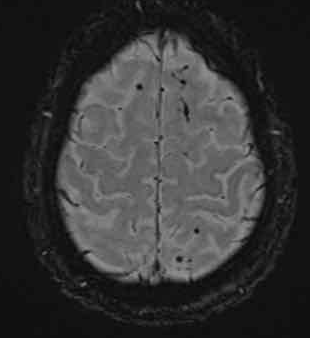

下图 一位46岁的男子骑摩托车时受伤。

瞳孔无反应性,瞳孔扩张。

CT:额叶点状出血。

继续做核磁共振成像

弥漫性轴索损伤(DAI)MRI表现

- 累及皮质下区、胼胝体、右侧丘脑和壳核、脑干、小脑脚和右侧小脑半球。

- 轻度全球萎缩。

MRI可准确诊断DAI,包括T2*GRE或SWI。

DAI在颅脑损伤患者MRI上的存在,更有可能导致不良的功能结局。

MRI可分为三个阶段:

- 脑叶白质可见病变

- 胼胝体损伤

- 脑干损伤

随着MRI分级的进行,不良预后也增加。

胼胝体病变尤其与不利的功能结局有关。